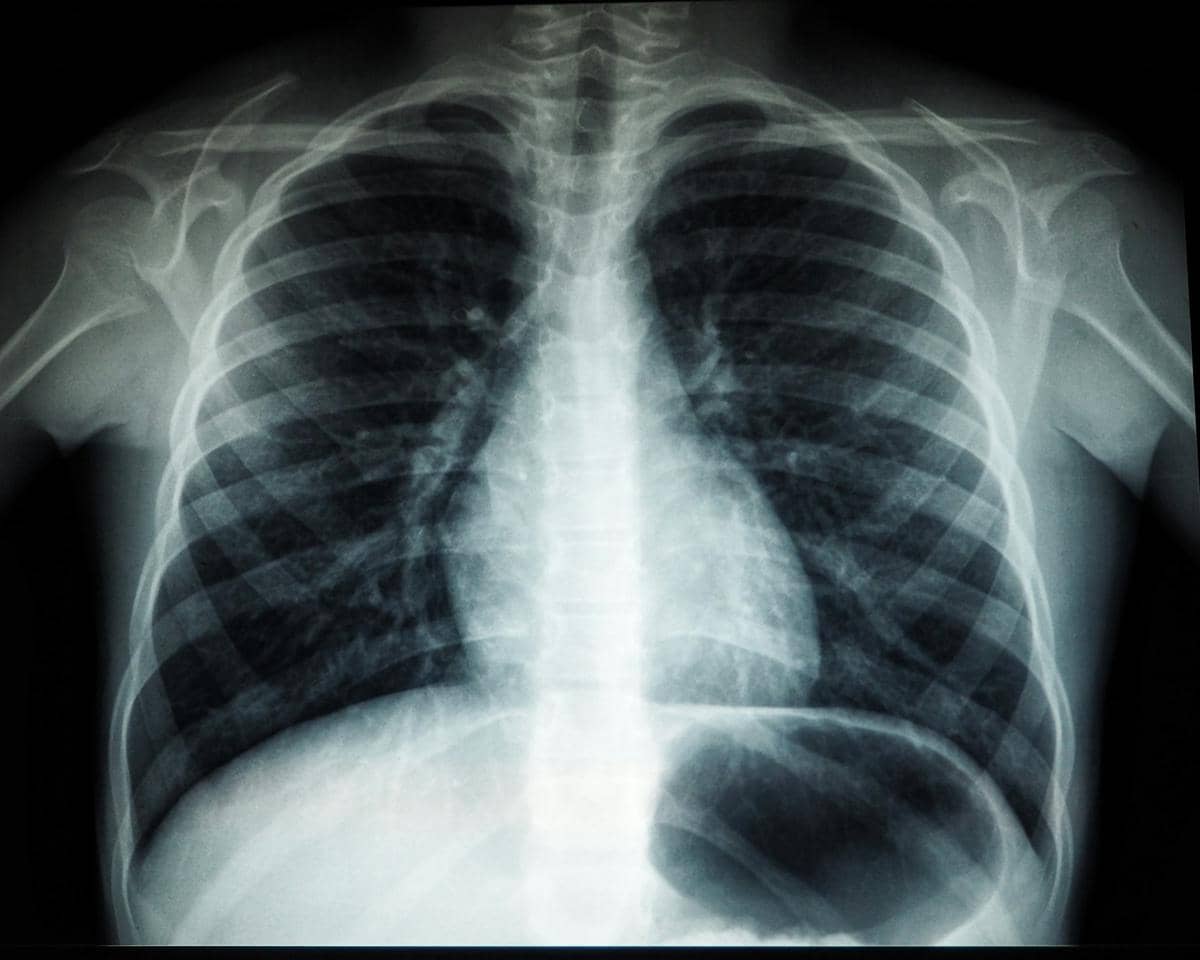

- Rontgen dada atau USG.

- Paru-paru (pulmonal): Infeksi paru, radang selaput paru, atau gangguan diafragma dapat menyebabkan nyeri dada, terutama saat bernapas.

- Nyeri saat bernapas, batuk berdahak kuning/hijau, demam: biasanya berkaitan dengan infeksi dada atau pneumonia.